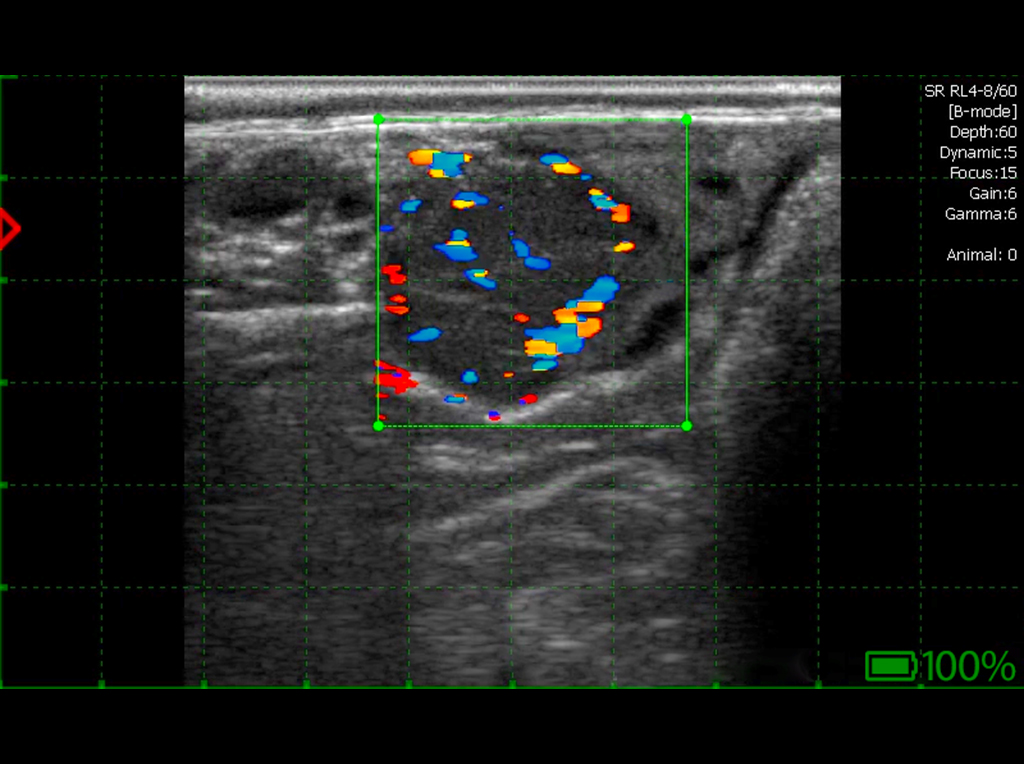

Kyste lutéal – paroi épaisse avec flux Doppler.

Kyste lutéal sur l’ovaire, épaisseur de la paroi supérieure à 3 mm. Tissu lutéal présent dans la paroi avec des flux Doppler.